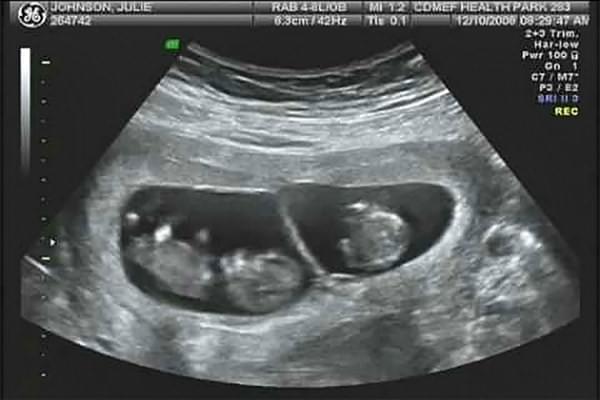

Наверняка определить количество плодов можно только по УЗИ. Исследование покажет также предлежание, размещение, тип и количество плацент и плодных мешков, объем амниотической жидкости, физическое состояние плодов и состояние кровотока в матке.

Из-за повышенной вероятности патологий УЗИ при многоплодной беременности делают чаще, чем при вынашивании одного ребенка. При монозиготной – каждые две недели, при двуяйцевой – 1 раз в месяц.